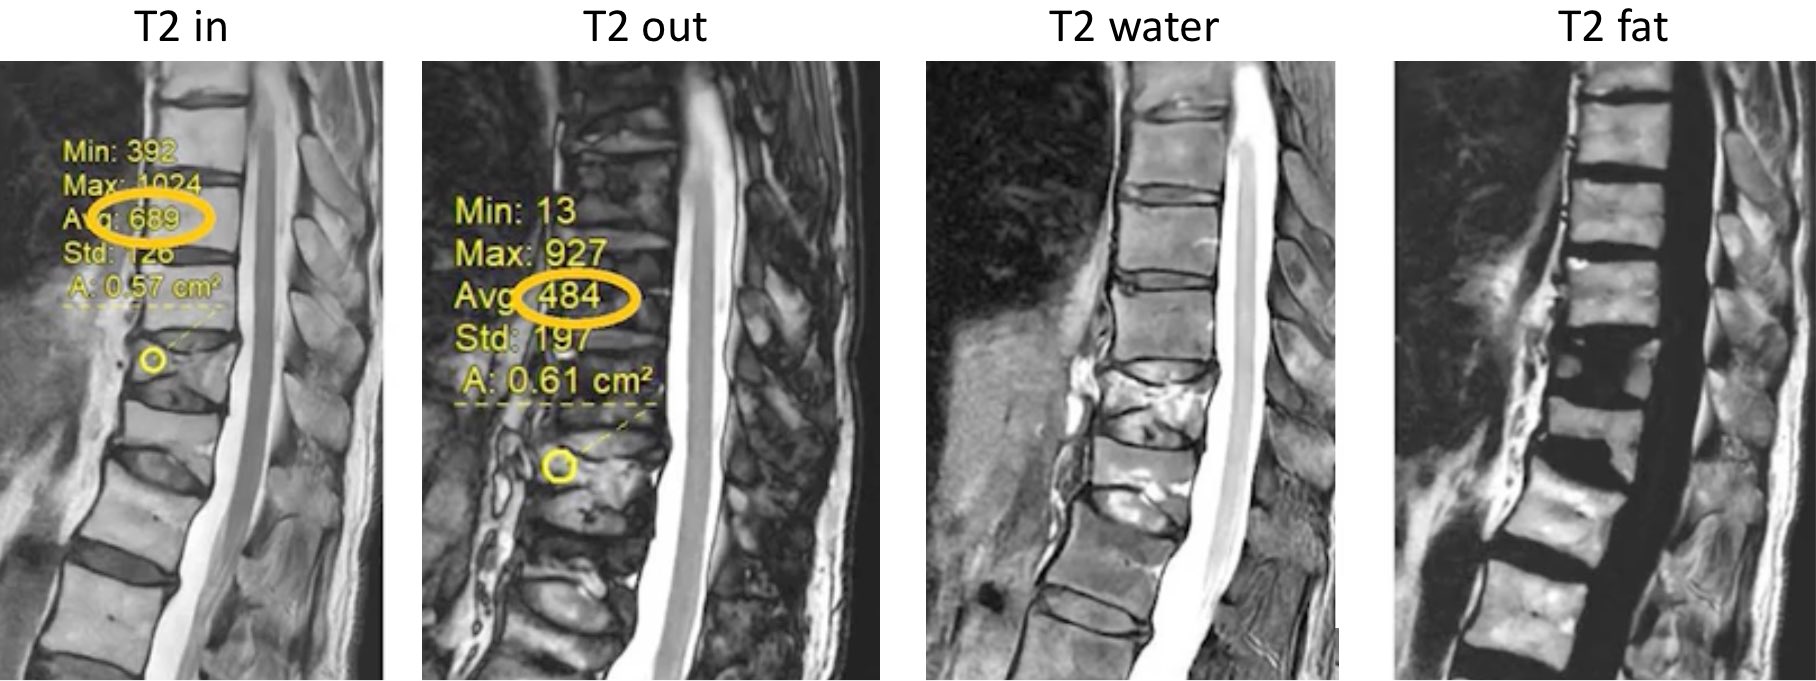

T2 Dixon = graisse si chute signal OP > 20% (# œdème d'une lésion tumorale)

T2 Dixon = graisse si chute signal OP > 20% (# œdème d'une lésion tumorale)